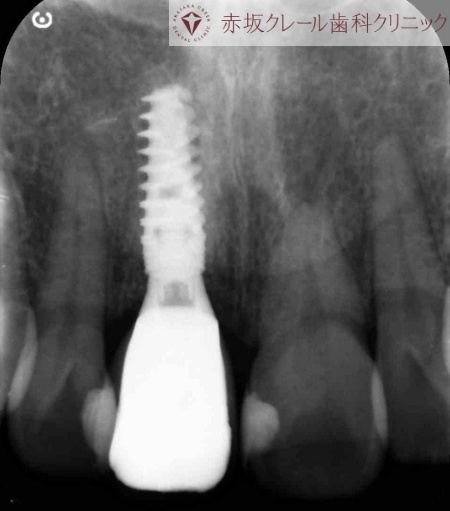

レントゲン検査を行った結果、歯根の先に膿がたまる根尖病巣(こんせんびょうそう)が確認できました。

今回のケースでは、根尖病巣があることに加え残っている歯の量がごくわずかであったため、再び被せ物で歯を修復することは難しく、抜歯が必要と診断しました。

手術当日は右上前歯の残っている歯を抜歯し、その直後にサージカルガイドを用いて計画した位置へインプラントを埋入しました。

抜歯した部分とインプラントの間には隙間ができるため、骨の再生を促す材料である骨補填材を入れて補強しています。